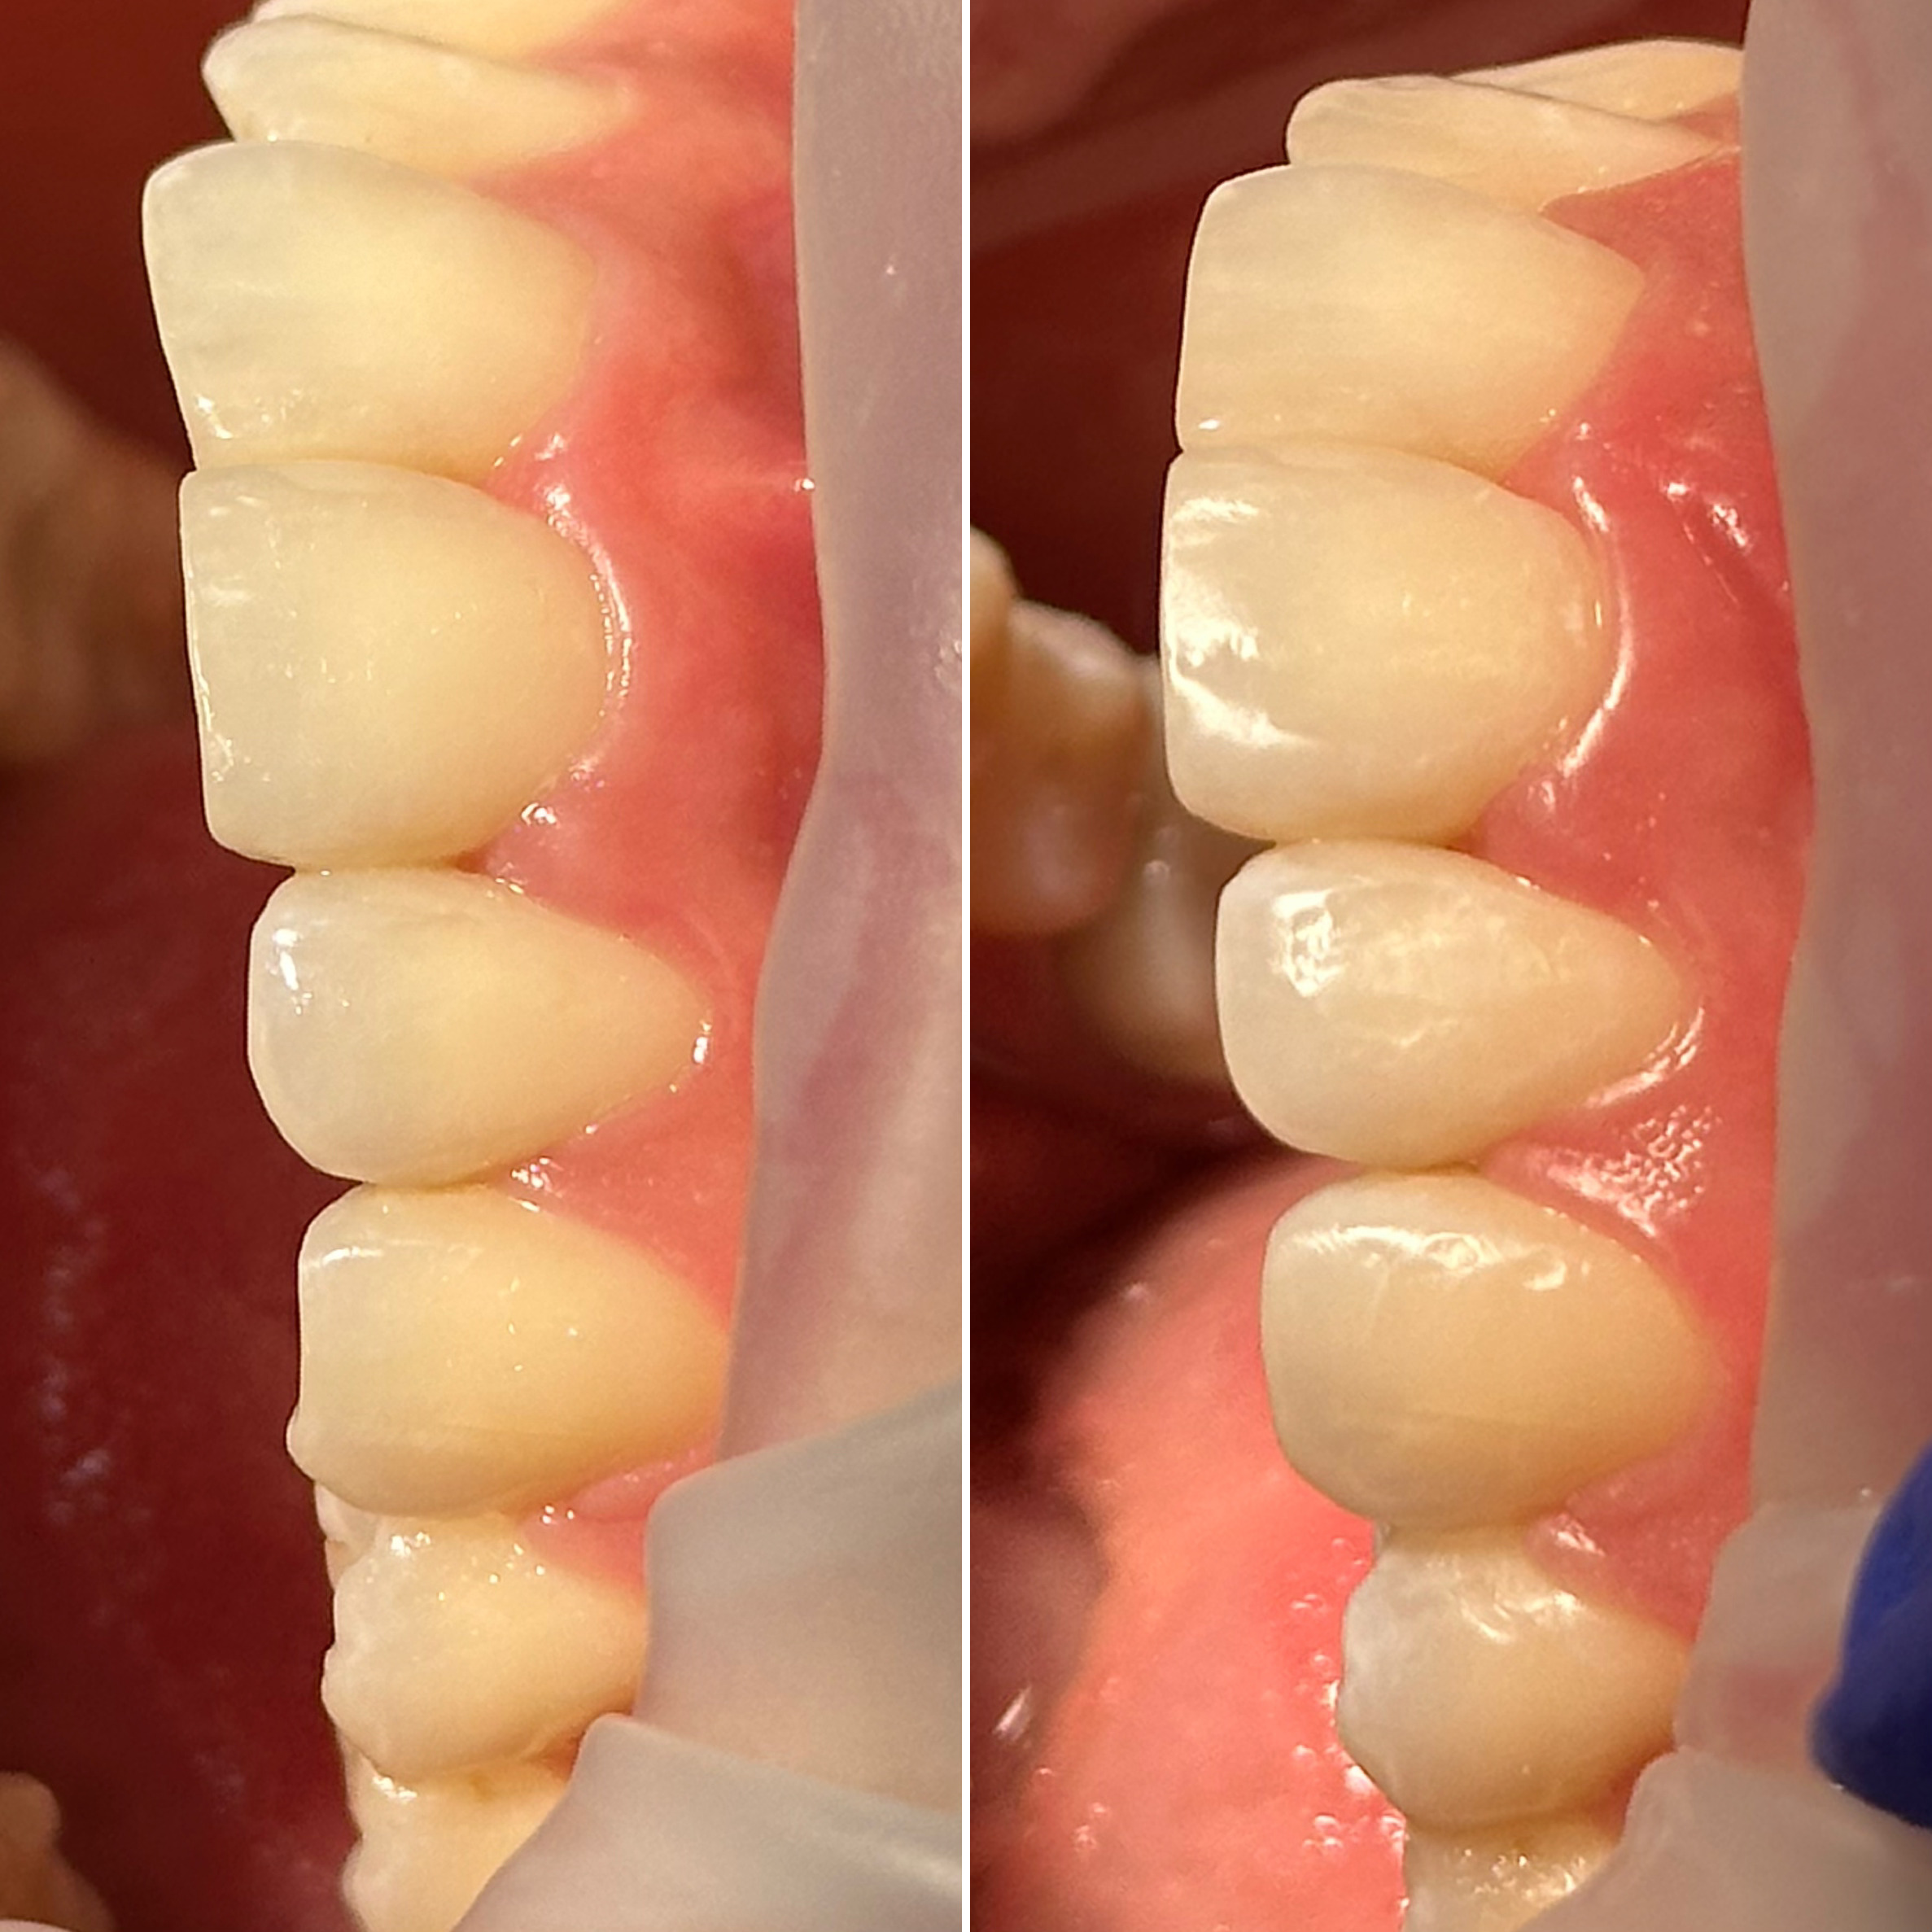

• Художественная реставрация фронтального и бокового участка зубов